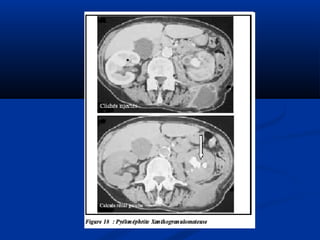

Vieâm thaän – beå thaänVieâm thaän – beå thaän

haït vaønghaït vaøng

 Sieâu aâm:Sieâu aâm:

• Theå lan toûa:Theå lan toûa:

• - Thaän phì ñaïi, giöõ nguyeân hình daïng, maát phaân bieät voû- Thaän phì ñaïi, giöõ nguyeân hình daïng, maát phaân bieät voû

– tuûy.– tuûy.

• - Nhieàu vuøng giaûm phaûn aâm töông öùng ñaøi thaän bò- Nhieàu vuøng giaûm phaûn aâm töông öùng ñaøi thaän bò

giaõn nôû hoaëc vuøng nhu moâ bò vieâmgiaõn nôû hoaëc vuøng nhu moâ bò vieâm

• - Ñoä thaáu aâm thay ñoåi theo möùc ñoä hoaù loûng cuûa caùc- Ñoä thaáu aâm thay ñoåi theo möùc ñoä hoaù loûng cuûa caùc

khoái nhu moâ.khoái nhu moâ.

• - Xoang thaän trung taâm coù theå taêng phaûn aâm roõ reät- Xoang thaän trung taâm coù theå taêng phaûn aâm roõ reät

keøm boùng löng töông öùng vôùi soûi san hoâ lôùn.keøm boùng löng töông öùng vôùi soûi san hoâ lôùn.